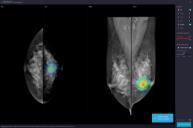

2013년 설립된 ’루닛‘은 국내 최초의 딥러닝 의료 AI 스타트업이다. 대표 제품은 ’Lunit INSIGHT‘로, 이는 딥러닝 기반 인공지능 기술을 활용해 흉부 X-ray를 분석하고, 폐 결절 및 유방암 등이 의심되는 이상 부위를 검출해주는 의료영상검출 보조 소프트웨어다.